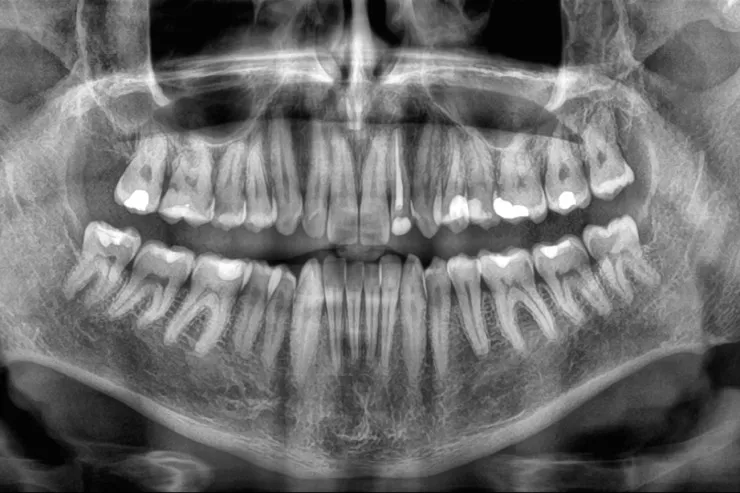

Yeni bir araşdırma göstərib ki, yaşlı insanlarda dişlərin sürətlə itirilməsi ölüm riskinin artması ilə əlaqəlidir. Çinli alimlər 3,5 il ərzində 8073 yaşlı insanı izləyərək belə nəticəyə gəliblər.

Lent.az “sciencealert.com” portalına istinadla xəbər verir ki, tədqiqatın nəticələrinə görə, dişlərin itirilmə sürəti nə qədər yüksəkdirsə, bütün səbəblərdən ölüm riski də bir o qədər artır. Bu əlaqə yaş, cins, təhsil, içki və məşq vərdişləri kimi digər amillər nəzərə alındıqdan sonra da qalır. Mütəxəssislər bildirirlər ki, dişlərin itirilməsi birbaşa ölümə səbəb olmur, lakin diş itkisinə yol açan sağlamlıq problemləri, məsələn, iltihab, pis qidalanma və ürək xəstəlikləri ömrü qısalda bilər. Alimlər diş itkisinin insanın ümumi sağlamlıq vəziyyətini qiymətləndirmək üçün göstərici kimi istifadə oluna biləcəyini vurğulayırlar. Həkimlər dişlərin qorunması üçün müntəzəm diş həkimi müayinəsini, gündə iki dəfə fırçalamağı və siqaretdən uzaq durmağı tövsiyə edirlər.

Araşdırma “BMC Geriatrics” jurnalında dərc olunub.